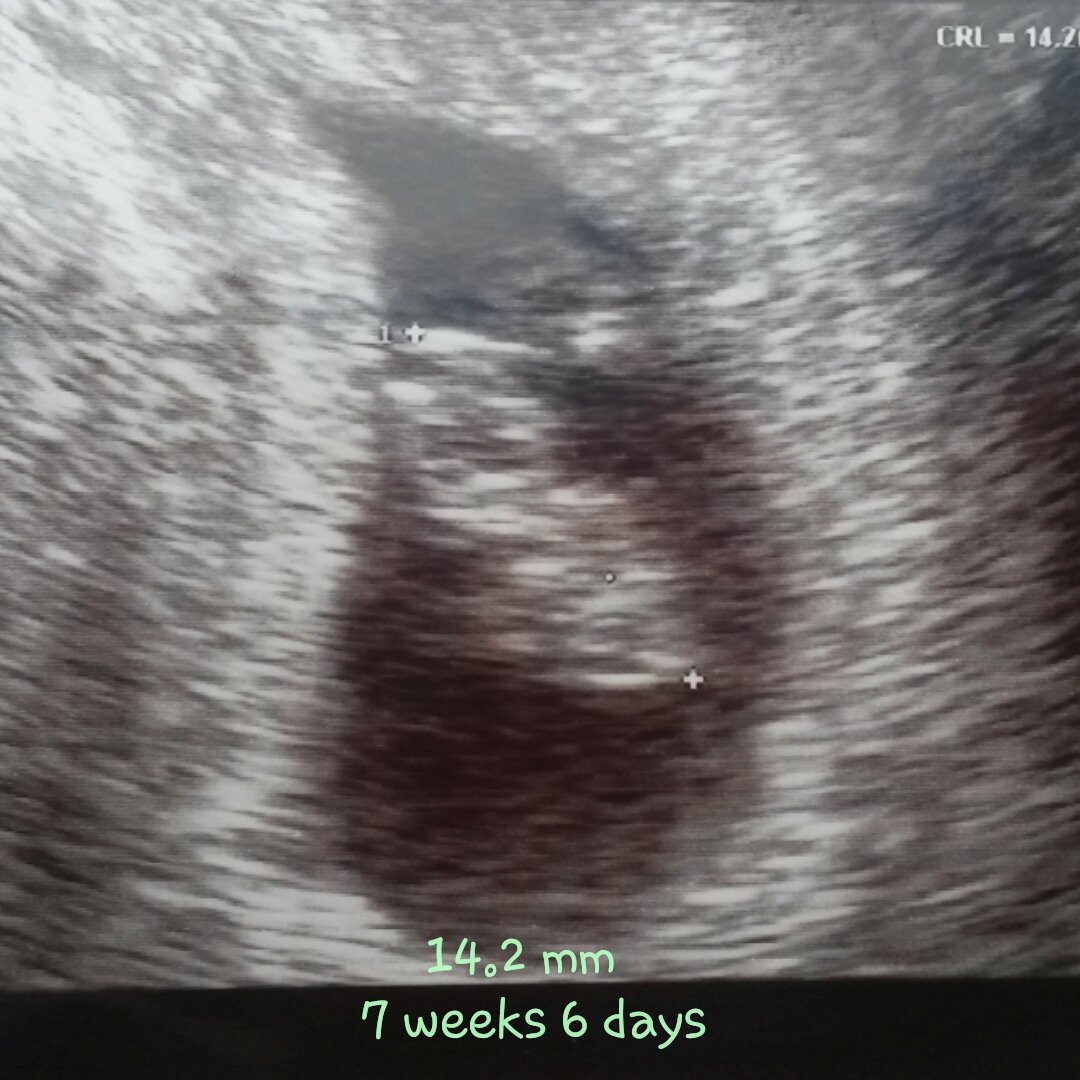

Rainbow Sugar Baby due 04/22/2016, C Section Scheduled for 04/08/2016